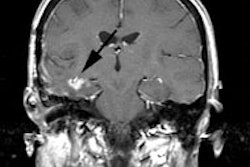

can be difficult to differentiate from residual or recurrent malignancy by MRI.

PET has been used to differentiate radiation injury from malignancy on the basis

of differences in glucose uptake. Recent studies have reported the sensitivity

and specificity of PET to be 81% to 86% and 40% to 94%, respectively. This